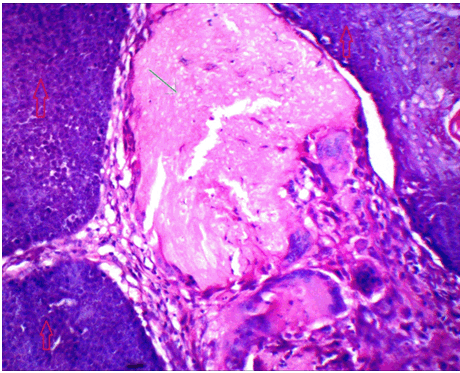

The clinical diagnosis in all the cases was suggestive of epidermoid/dermoid cyst. However, subsequent histopathologic examination confirmed these cases as pilomatricoma. All the lesions were well encapsulated. H&E sections showed dual population of cells comprising the peripheral basaloid cells and the ghost or shadow cells in the centre (Figure 1). A transition of basaloid to ghost cells was noted in many areas. Sections from the right eyebrow swelling posed great difficulty in diagnosis since there were mainly ghost cells present and almost negligible basophilic cells representing stage 4 (Figure 2). The remaining four cases (80%) belonged to the third morphological stage. Two cases showed a rich infiltrate of lymphoplasmacytic cells and numerous foreign body giant cells near the shadow cells (Figure 3). Three cases showed areas of calcification.

Figure 1: Uniform population of small basophilic cells (Ý) and another area of large shadow/ghost cells filled with keratin and cell debris (↑ ). (H&E stain, x100).